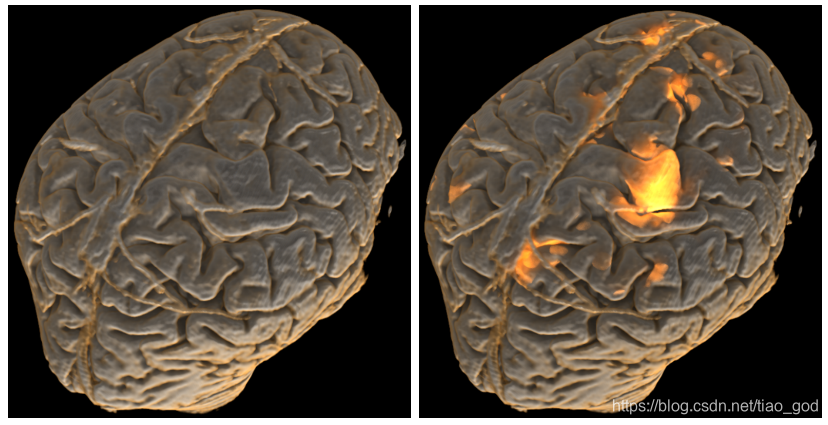

上图中,左边的![]() 只有一个外部环境照明。右边的

只有一个外部环境照明。右边的![]() 包含了emission项,它的设置与fMRI信号的信号强度成正比。

包含了emission项,它的设置与fMRI信号的信号强度成正比。